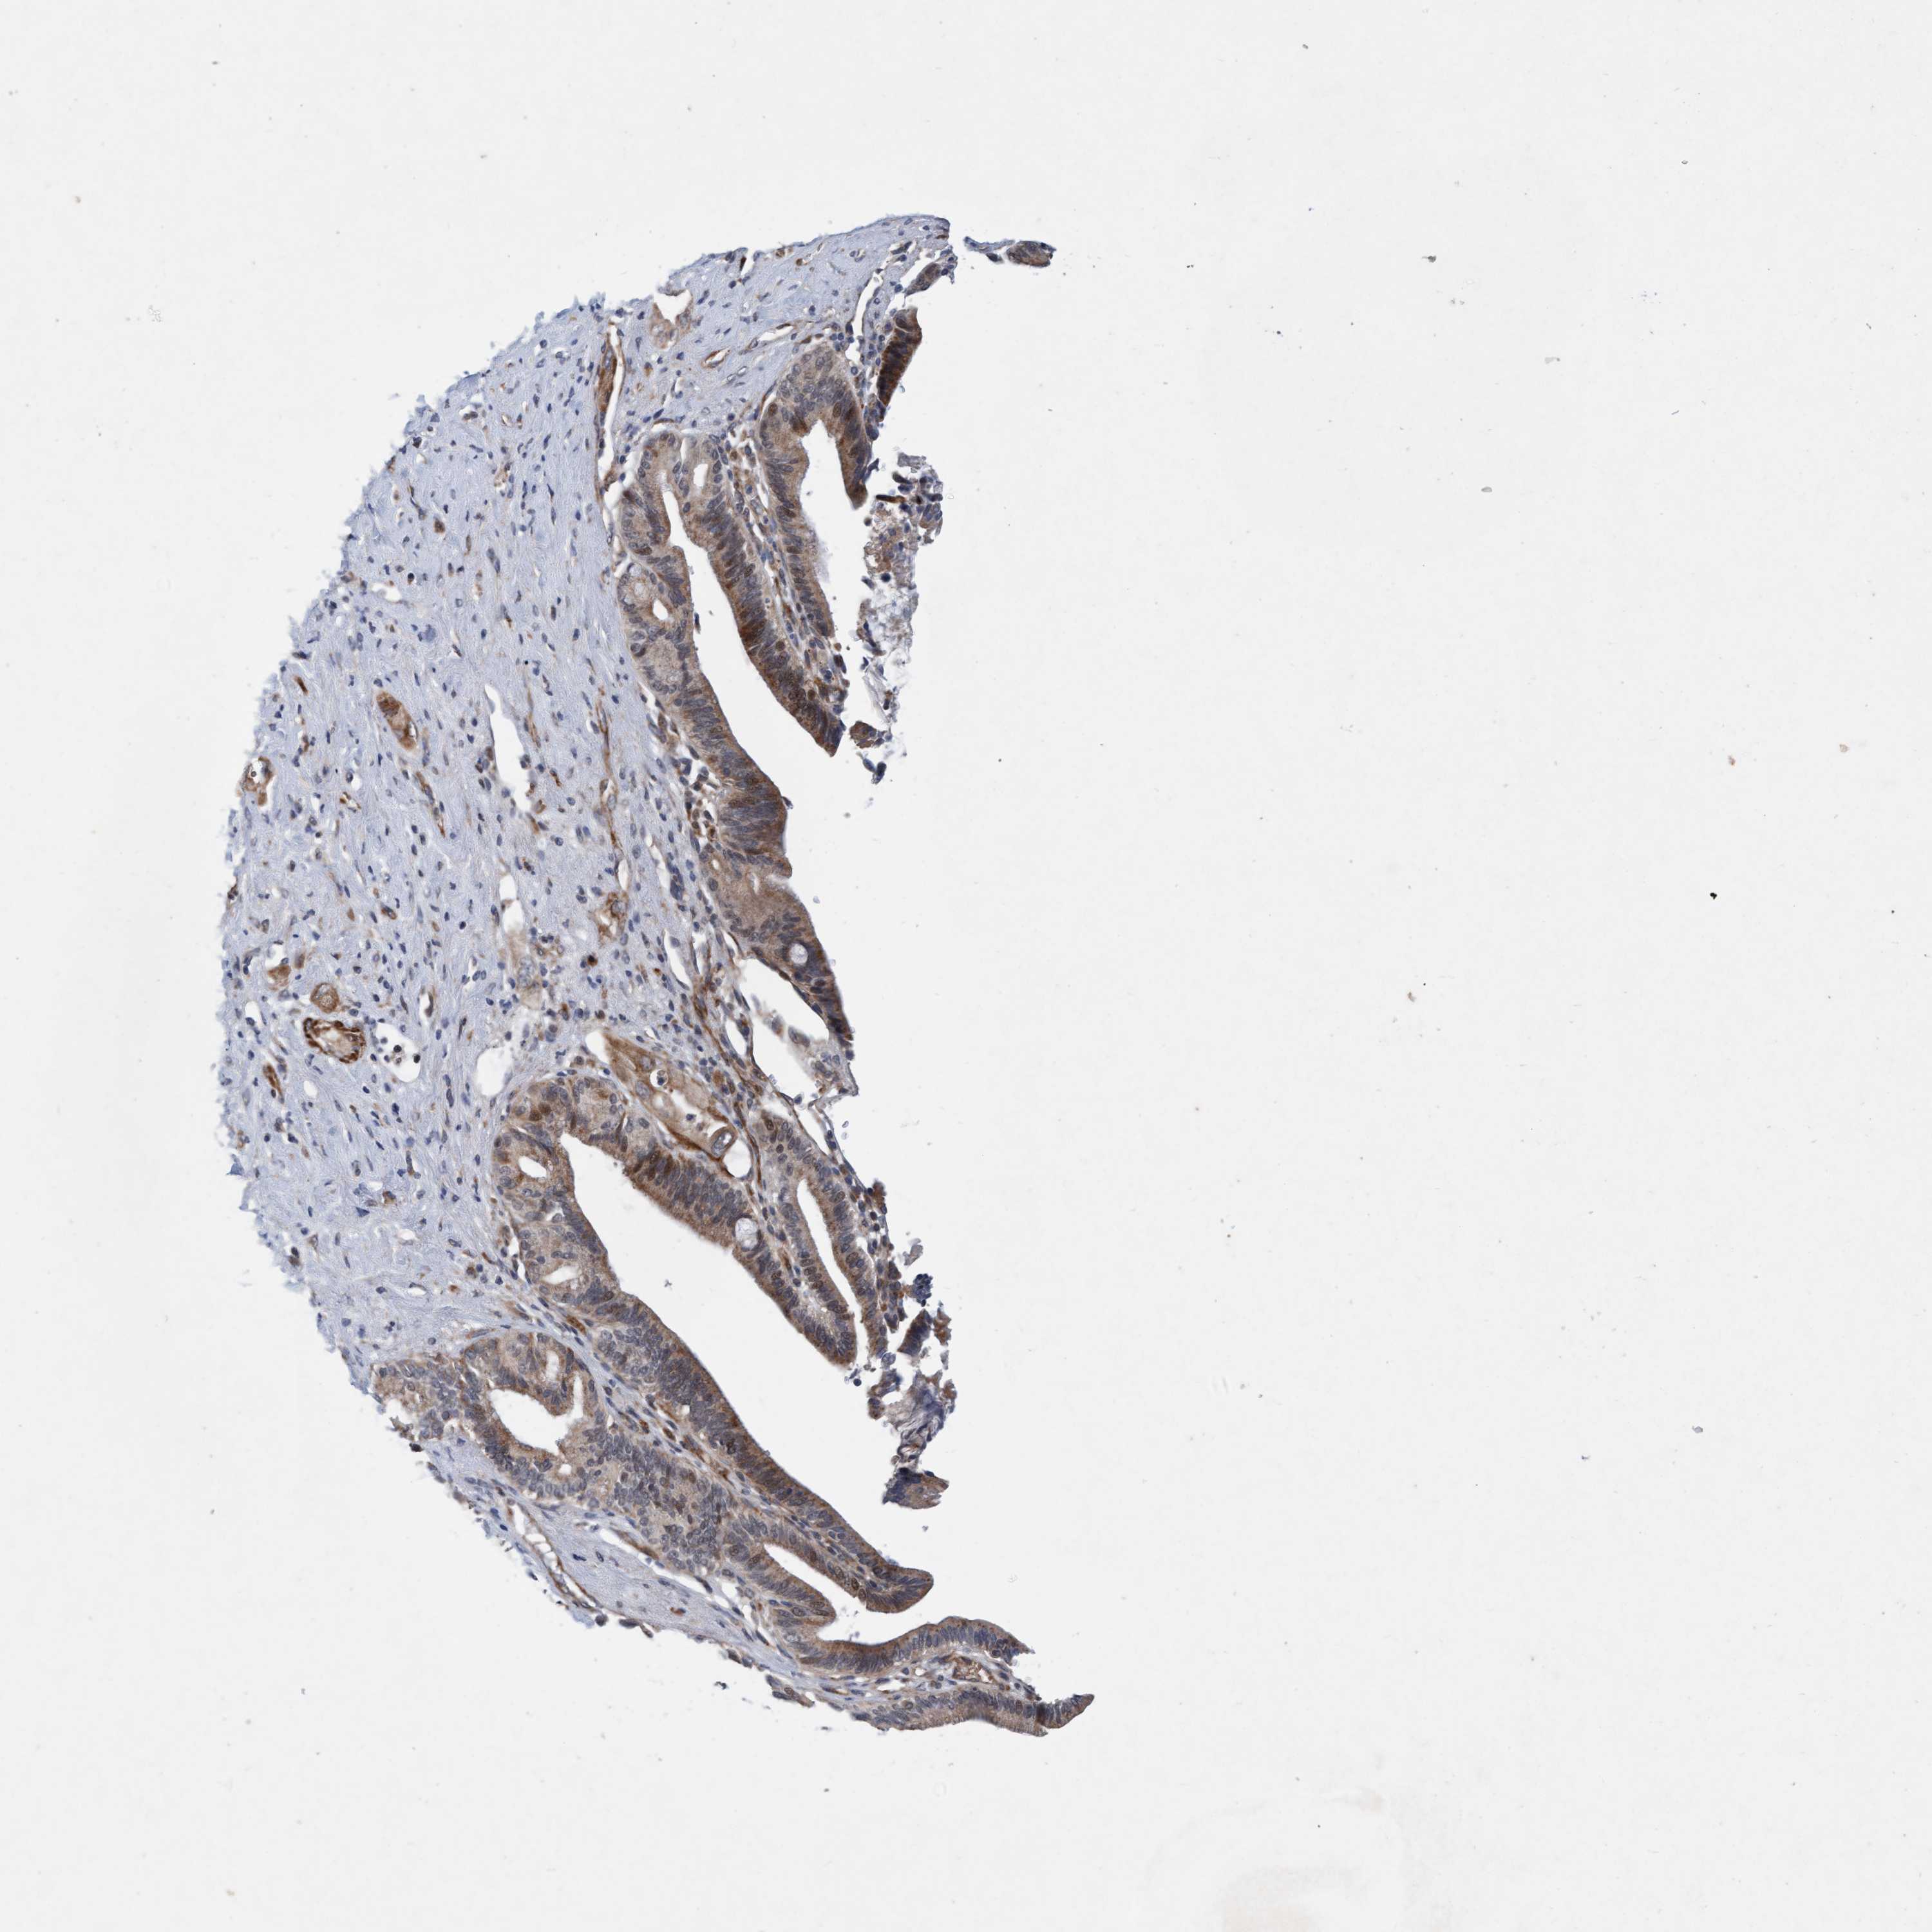

PANCREATIC CANCER - Protein expressioni

A mouse-over function shows sample information and annotation data. Click on an image to view it in a full screen mode. Samples can be filtered based on level of antibody staining by selecting one or several of the following categories: high, medium, low and not detected. The assay and annotation is described here.

Note that samples used for immunohistochemistry by the Human Protein Atlas do not correspond to samples in the TCGA dataset.

Antibody stainingi

Antibody staining in the annotated cell types in the current human tissue is reported as not detected, low, medium, or high, based on conventional immunohistochemistry profiling in selected tissues. This score is based on the combination of the staining intensity and fraction of stained cells.

Each image is clickable and will lead to virtual microscopy that enables deeper exploration of all samples and also displays staining intensity scores, fraction scores and subcellular localization as well as patient and tissue information for each sample.

Antibody HPA023187

Antibody CAB034226

Staining

High

Medium

Low

Not detected

Adenocarcinoma, NOS